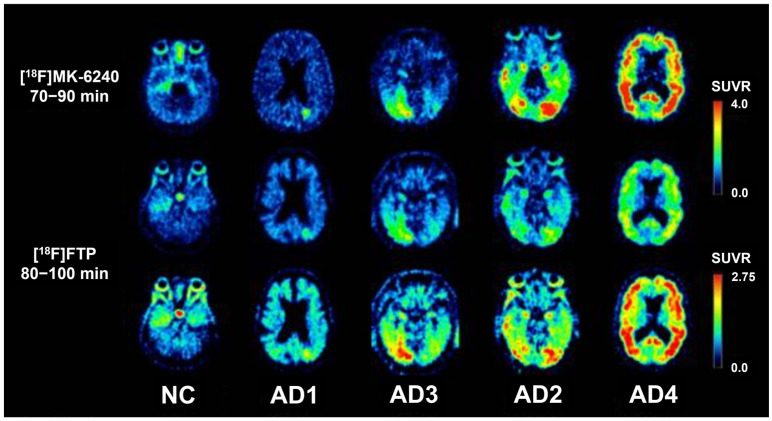

Alzheimer's disease (AD) affects an estimated 6.9 million older adults in the United States and is projected to impact as many as 13.8 million people by 2060. As studies continue to search for ways to combat the development and progression of AD, it is imperative to ensure that confident diagnoses can be made before the onset of severe clinical symptoms and new therapies can be evaluated effectively. Tau positron emission tomography (PET) has emerged as one method that may be capable of both, given its ability to recognize the presence of tau, a primary pathologic hallmark of AD; its usefulness in determining the spatial distribution of tau, which is necessary for differentiating AD from other tauopathies; and its association with measures of cognition. This review aims to evaluate the scope of tau PET's utility in clinical trials and practice. Firstly, the potential of using tau PET for differential diagnoses, distinguishing AD from other dementias, is considered. Next, the value of tau PET as a tool for staging disease progression is investigated. Finally, tau PET as a prognostic method for identifying the individuals most at risk of cognitive decline and, therefore, most in need of, and likely to benefit from, intervention, is discussed.